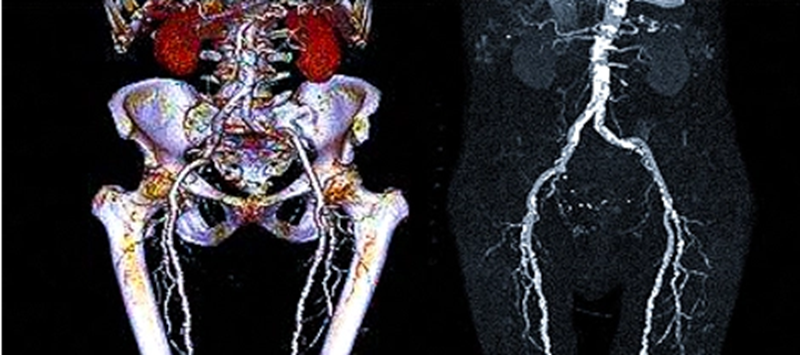

При исследовании КТ-ангиография создается детализированная модель сосудистого русла в нескольких проекциях. Это позволяет максимально точно оценить состояние не только подвздошных артерий, но и всех артерий нижних конечностей, выявить патологии на максимально возможной ранней стадии патологии. КТ-ангиография артерий нижних конечностей позволяет:

После получения снимков данные КТ ангиографии обрабатываются программами для получения более информативных трехмерных изображений и многоплоскостных реконструкций. Уникальный метод КТ ангиографии позволяет построить 3D-модель сосудов, что позволяет более точно оценить степень распространения патологий.

КТ ангиография для исследования состояния подвздошных артерий позволяет детализировано изучить анатомические особенности кровеносного русла. Подвздошная артерия является парным сосудом, начинающимся на уровне IV-го позвонка поясницы на участке раздвоения брюшной аорты. Ветви несимметричны, правая длиннее левой на 7 мм. На линии крестцово-подвздошного сочленения русло делится на ветви: наружную и внутреннюю. Наружная питает сосуды нижних конечностей. Внутренняя - органы малого таза.